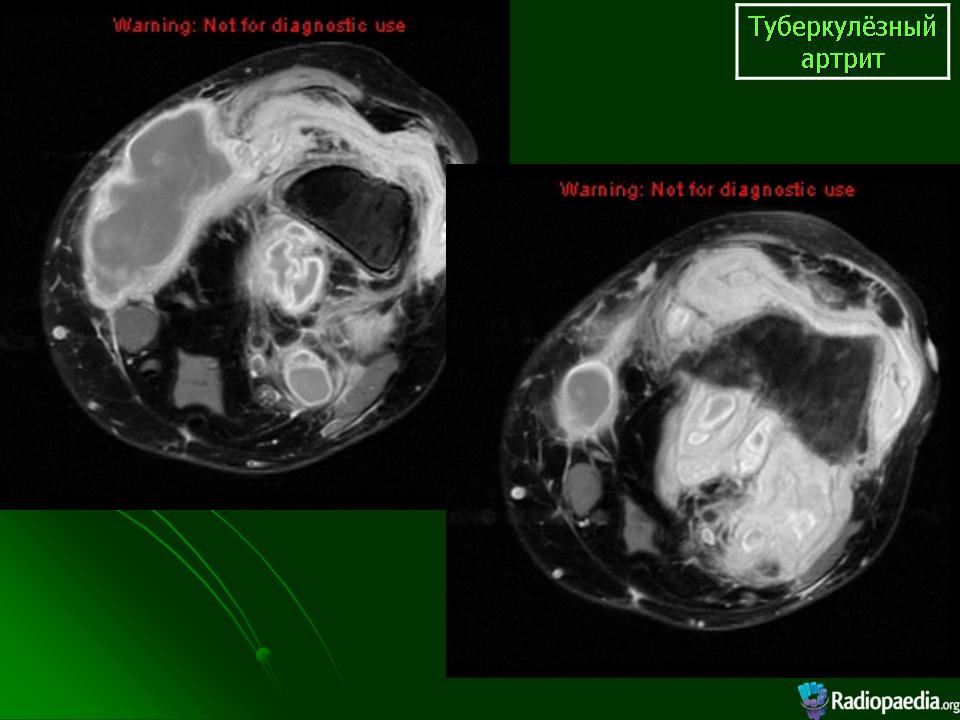

Туберкулез коленного сустава (гонит)

Поражение коленного сустава при туберкулезе встречается часто, на его долю приходится около 20% всех случаев костно-суставного туберкулеза. Общие клинические симптомы в преартритической фазе связаны с интоксикацией. Местные проявления или совсем отсутствуют, или носят неопределенный характер и мало выражены, однако больной заметно щадит пораженную конечность. Преартритическая фаза может протекать длительно, особенно в детском возрасте, в связи с тем, что эпифизы покрыты толстым суставным хрящом. Первичные очаги чаще встречаются в проксимальном эпифизе большеберцовой кости (50%) и в дистальном эпифизе бедренной кости (21,7%), реже в метафизах этих костей (соответственно в 10% и 2,3% случаев), и совсем редко в надколеннике и эпифизе малоберцовой кости (2,2%). Первым рентгенологическим симптомом туберкулезного процесса является ограниченный участок остеопороза с нечетким рисунком костных трабекул. Затем появляется нечетко очерченный очаг деструкции костной ткани, который может содержать губчатые мелкие секвестры. Очаги деструкции могут быть крупными, нередко в форме песочных часов, что характерно именно для поражения коленного сустава. При наиболее частой, эпиметафизарной локализации, очаги деструкции костной ткани обычно располагаются субкортикально. Периоститы не характерны. Артритическая фаза туберкулезного гонита характеризуется постоянством клинических проявлений. Появляется небольшая атрофия мышц, симптом Александрова, припухлость и боли в суставе, контрактуры, повышение местной температуры. Причем эти симптомы сохраняются и в покое. У некоторых детей отмечается удлинение пораженной конечности. Сустав увеличен в объеме, постепенно нарастает атрофия мышц, подвывихи голени, чаще кзади. Появляются натечные абсцессы и свищи. Рентгенологические проявления туберкулезного гонита достаточно разнообразны. Однако самым ранним симптомом перехода туберкулезного процесса на сустав является нарастающий диффузный или пятнистый остеопороз, который постепенно распространяется на кости всей конечности. Причем, чем более остро протекает туберкулезный процесс, тем более выражен остеопороз. У детей отмечается увеличение размеров эпифизов, по сравнению со здоровой конечностью, одновременно может увеличиваться ядро окостенения надколенника (симптом «постарения эпифизов» С. Л. Трегубова). Постепенно нарастает сужение суставной щели, которое иногда может быть неравномерным, больше выраженным с одной стороны. Однако этот признак иногда может быть кажущимся, и связан с небольшой сгибательной контрактурой. В таких случаях необходимо производить для сравнения рентгенографию и здорового коленного сустава в том же положении. Одновременно с сужением суставной щели появляется неровность, волнистость суставных поверхностей, затем появляется нечеткость, зазубренность, прерывистость контуров суставных поверхностей. Выявляются краевые очаги деструкции костной ткани, которые могут располагаться в противоположных отделах сочленяющихся костей и содержать секвестры, часто множественные. Секвестры кажутся более плотными, «склерозированными» на фоне выраженного остеопороза, структура их губчатая, «ноздреватая», контуры неровные. Постепенно появляются признаки истинной атрофии костей. При затихании процесса рентгенологически не отмечается прогрессирование деструкции. Контуры очагов деструкции становятся сначала четкими, а затем вокруг них появляется нежный ободок склероза. Выявляются контуры суставной щели, которая имеет причудливую форму. На уровне очагов деструкции она неравномерно расширена, а в тех отделах, где замыкательные пластинки эпифизов сохранены резко сужена. На фоне остеопороза появляются толстые, склерозированные костные балки, расположенные вдоль силовых линий. Постепенно восстанавливаются и уплотняется замыкательнные пластинки эпифизарных концов сочленяющихся костей. Суставная щель суживается, иногда вовсе не прослеживается. Костные анкилозы наблюдаются не часто, более типичны фиброзные сращения, порочное положение и подвывихи. У детей нарушается продольный рост костей и отмечается их укорочение. В менее благоприятных случаях наблюдаются обострения и рецидивы, что связано с наличием остаточных туберкулезных очагов. В этих случаях нарастают явления интоксикации и местные изменения. При рентгенологическом исследовании выявляется нарастание остеопороза, появляются очаги деструкции с нечеткими, неровными контурами, иногда содержащие секвестры. Замыкательные пластинки также теряют четкость. Деструктивные изменения могут быть значительными и приводить к дальнейшему разрушению костей, образующих сустав. Дифференциальную диагностику туберкулезного гонита приходится проводить с целым рядом заболеваний: частичным асептическим некрозом (болезнь Кенига), литическим вариантом остеобластокластомы, остеогенной остеокластической саркомой, гемофилическим артрозом и ревматоидным артритом. Болезнь Кенига встречается у взрослых. Больных беспокоят боли в коленном суставе, усиливающиеся при нагрузке. Симптомы интоксикации отсутствуют. Дифференцировать с туберкулезным процессом приходится I—II стадии болезни Кенига. Однако отсутствие остеопороза, типичная локализация краевого очага деструкции в медиальном мыщелке бедра, его небольшие размеры, относительно четкие контуры, наличие плотного с четкими контурами секвестроподобного тела, обычные размеры суставной щели — все это позволяет высказаться в пользу частичного асептического некроза. При дифференциальной диагностике с остеогенной остеокластической саркомой, которая особенно в начальных стадиях протекает без постоянных болей, может возникнуть ряд трудностей. Однако у детей остеогенная саркома локализуется в метафизе. Очаг деструкции одиночный с неровными, нечеткими контурами, не содержит секвестров, остеопороз в прилежащих отделах костной ткани не характерен. Типична периостальная реакция по смешанному типу. Раньше существовала точка зрения, что при саркоме процесс не переходит через ростковую зону. В последние годы доказана возможность у детей перехода процесса при остеогенной саркоме через ростковую зону. Однако разрушения суставного хряща и сужения суставной щели не отмечается. При литическом варианте остеобластокластомы очаг деструкции костной ткани, локализуясь в эпиметафизе у взрослых и метадиафизе у детей, чаще располагается эксцентрично, вызывая на ранних стадиях асимметричное булавовидное вздутие кости. Очаг деструкции имеет четкие контуры. Склеротическое отграничение и наличие секвестров не типично. Остеопороза в прилежащих отделах не выявляется. При проведении дифференциальной диагностики с гемофилическим артрозом необходимо учитывать клинические, анамнестические и лабораторные данные. У больных с гемартрозом отсутствуют явления интоксикации, в анамнезе имеется указание на кровоточивость, свертываемость крови замедлена. Кроме того, при гемофилии, как правило, поражаются несколько суставов. При рентгенологическом исследовании может выявляться остеопороз, который захватывает эпифизы и не бывает таким распространенным, как при туберкулезе. Может наблюдаться увеличение размеров эпифизов по сравнению со здоровой стороной. Контуры замыкательных пластинок неровные, но всегда четкие, секвестры отсутствуют. В ряде случаев может возникнуть необходимость в проведении дифференциальной диагностики с ревматоидным артритом,, который в детском возрасте иногда может начинаться с поражения одного сустава. В этих случаях необходимо учитывать длительность заболевания, клинические и лабораторные данные. При ревматоидном артрите характерна скованность движений по утрам, отсутствие симптомов интоксикации, отрицательный симптом Александрова. Туберкулиновые пробы, как правило, отрицательные. Диагностическое значение имеет положительный ревматоидный фактор в синовиальной жидкости. При рентгенологическом исследовании больных ревматоидные артритом выявляется остеопороз костей образующих коленный сустав, сужение суставной щели. У мест прикрепления капсулы сустава выявляются краевые узуры с четкими контурами и ободком склероза вокруг. При туберкулезном гоните — в эпиметафизе большеберцовой и бедренной костей выявляются очаги деструкции с нечеткими, изъеденными контурами, постепенно переходящими в остеопоротичную костную ткань. Очаги деструкции могут содержать губчатые секвестры.